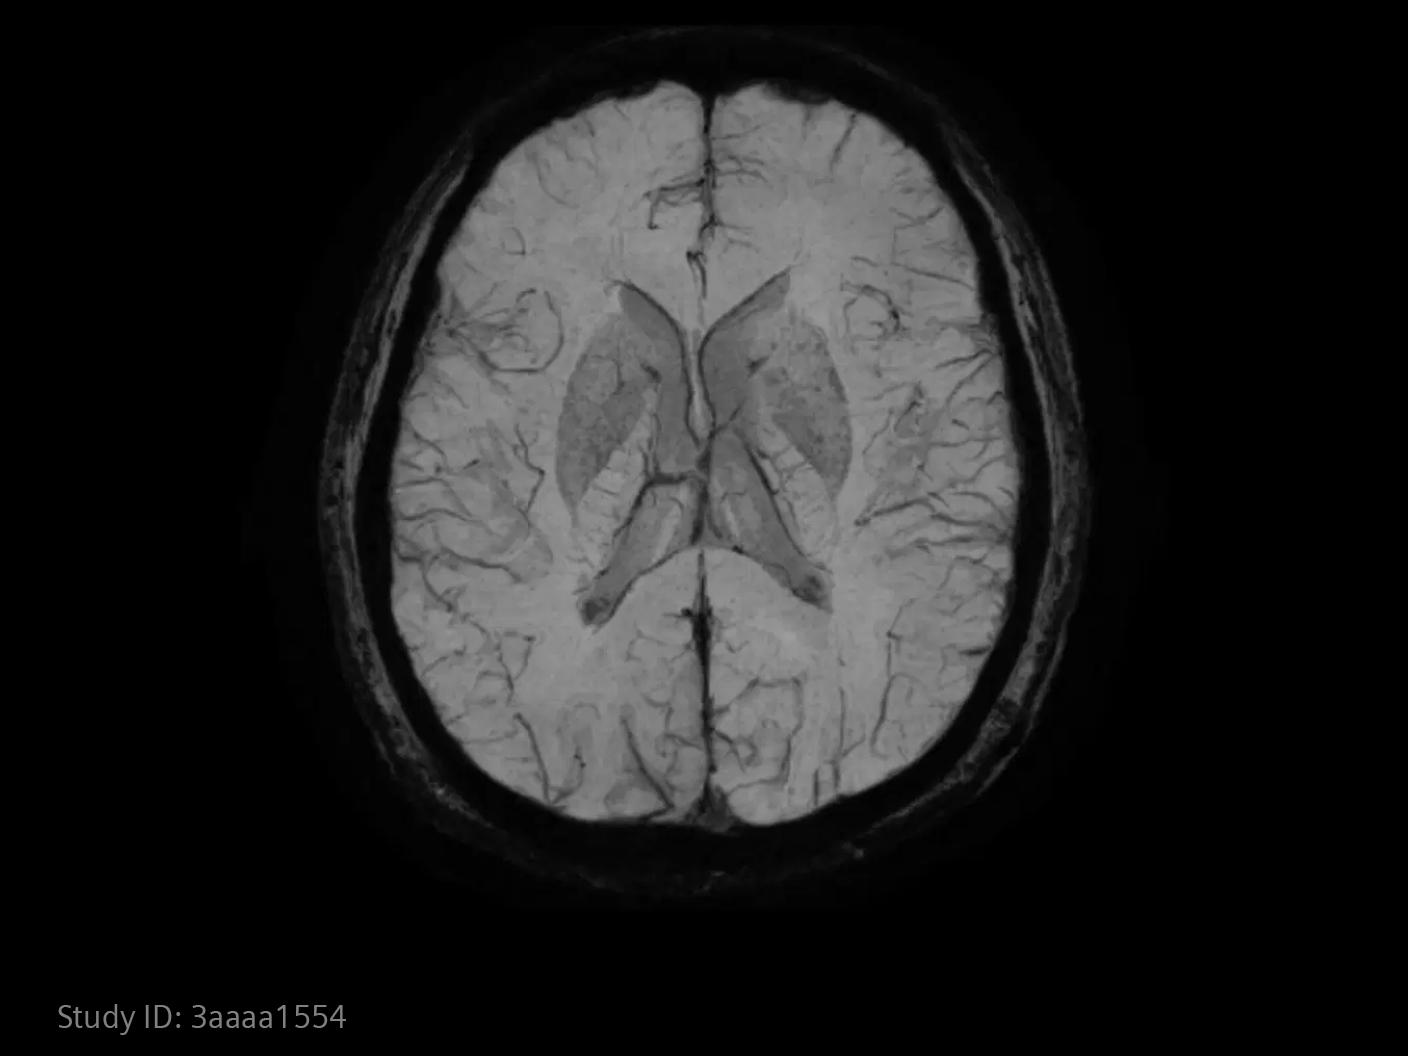

Im Bereich der Schlaganfallversorgung zählt jede Sekunde . Schnelle und präzise Bildgebung ist entscheidend, um das Ausmaß der Hirnschädigung zu beurteilen und die sofortige Behandlung einzusteuern. Angiographie, MRT, CT, Labordiagnostik und Ultraschall sind unverzichtbare Werkzeuge, um Schlaganfalltyp, -bereich und -schwere zu bestimmen. Durch technologische Fortschritte in der Bildgebung sind heute noch schnellere Aufnahmen, eine bessere Auflösung und eine optimierte Darstellung von Gehirnstrukturen und Blutgefäßen möglich. Innovationen wie Perfusionsbildgebung, Echtzeit-Gefäßkartierung und KI-gestützte Diagnostik revolutionieren die Abläufe bei Schlaganfällen und ermöglichen präzise zeitnahe Interventionen.